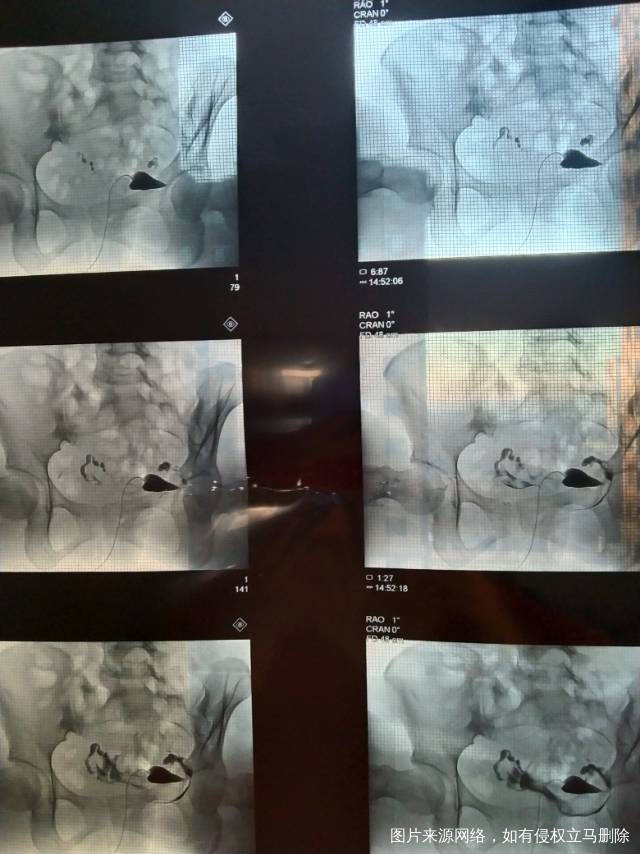

做完输卵管造影第六天了小腹还是感觉沉甸甸的如

可以热敷腹部,如果有发热,腹痛加剧,白带量多,有异味,随时就医